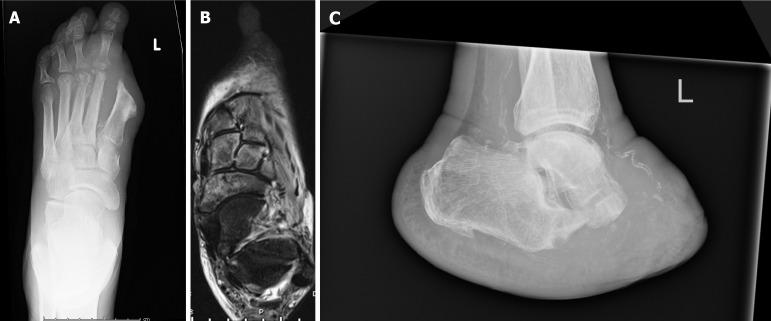

The prevalence of diabetes mellitus and its associated complications, particularly diabetic foot pathologies, poses significant healthcare challenges and economic burdens globally. This review synthesises current evidence on the surgical management of the diabetic foot, focusing on the interplay between neuropathy, ischemia, and infection that commonly culminates in ulcers, infections, and, in severe cases, amputations. The escalating incidence of diabetes mellitus underscores the urgency for effective management strategies, as diabetic foot complications are a leading cause of hospital admissions among diabetic patients, significantly impacting morbidity and mortality rates. This review explores the pathophysiological mechanisms underlying diabetic foot complications and further examines diabetic foot ulcers, infections, and skeletal pathologies such as Charcot arthropathy, emphasising the critical role of early diagnosis, comprehensive management strategies, and interdisciplinary care in mitigating adverse outcomes. In addressing surgical interventions, this review evaluates conservative surgeries, amputations, and reconstructive procedures, highlighting the importance of tailored approaches based on individual patient profiles and the specific characteristics of foot pathologies. The integration of advanced diagnostic tools, novel surgical techniques, and postoperative care, including offloading and infection control, are discussed in the context of optimising healing and preserving limb function.

糖尿病及其相关并发症,尤其是糖尿病足病变的患病率,在全球范围内构成了重大的医疗挑战和经济负担。本综述综合了关于糖尿病足手术治疗的现有证据,重点关注神经病变、缺血和感染之间的相互作用,这些因素通常最终导致溃疡、感染,严重时还会导致截肢。糖尿病发病率的不断上升凸显了有效管理策略的紧迫性,因为糖尿病足并发症是糖尿病患者住院的主要原因,对发病率和死亡率有重大影响。本综述探讨了糖尿病足并发症的病理生理机制,并进一步研究了糖尿病足溃疡、感染和夏科关节病等骨骼病变,强调了早期诊断、综合管理策略和跨学科护理在减轻不良后果方面的关键作用。在讨论手术干预措施时,本综述评估了保守手术、截肢和重建手术,强调了根据个体患者情况和足部病变的具体特征采取定制方法的重要性。在优化愈合和保留肢体功能的背景下,讨论了先进诊断工具、新型手术技术和术后护理(包括减负和感染控制)的整合。